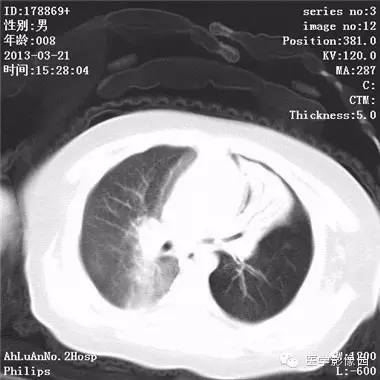

患儿男,8个月,呛咳,发热一周。实验室检查白细胞及中性粒细胞增高。

两肺肺纹理增多、增粗,右肺可见斑片状、片絮状模糊影,边界欠清;左肺上叶见楔形高密度影,内可见支气管征,尖端指向肺门;左肺下叶肺野透亮度增强;另见左肺主支气管内可见块状软组织密度影。

支气管异物(花生米)伴两肺炎症(追问病史,患儿奶奶层于一周前喂食患儿花生米,当时疑似“呛进去”,后来见好了也就没留意)。